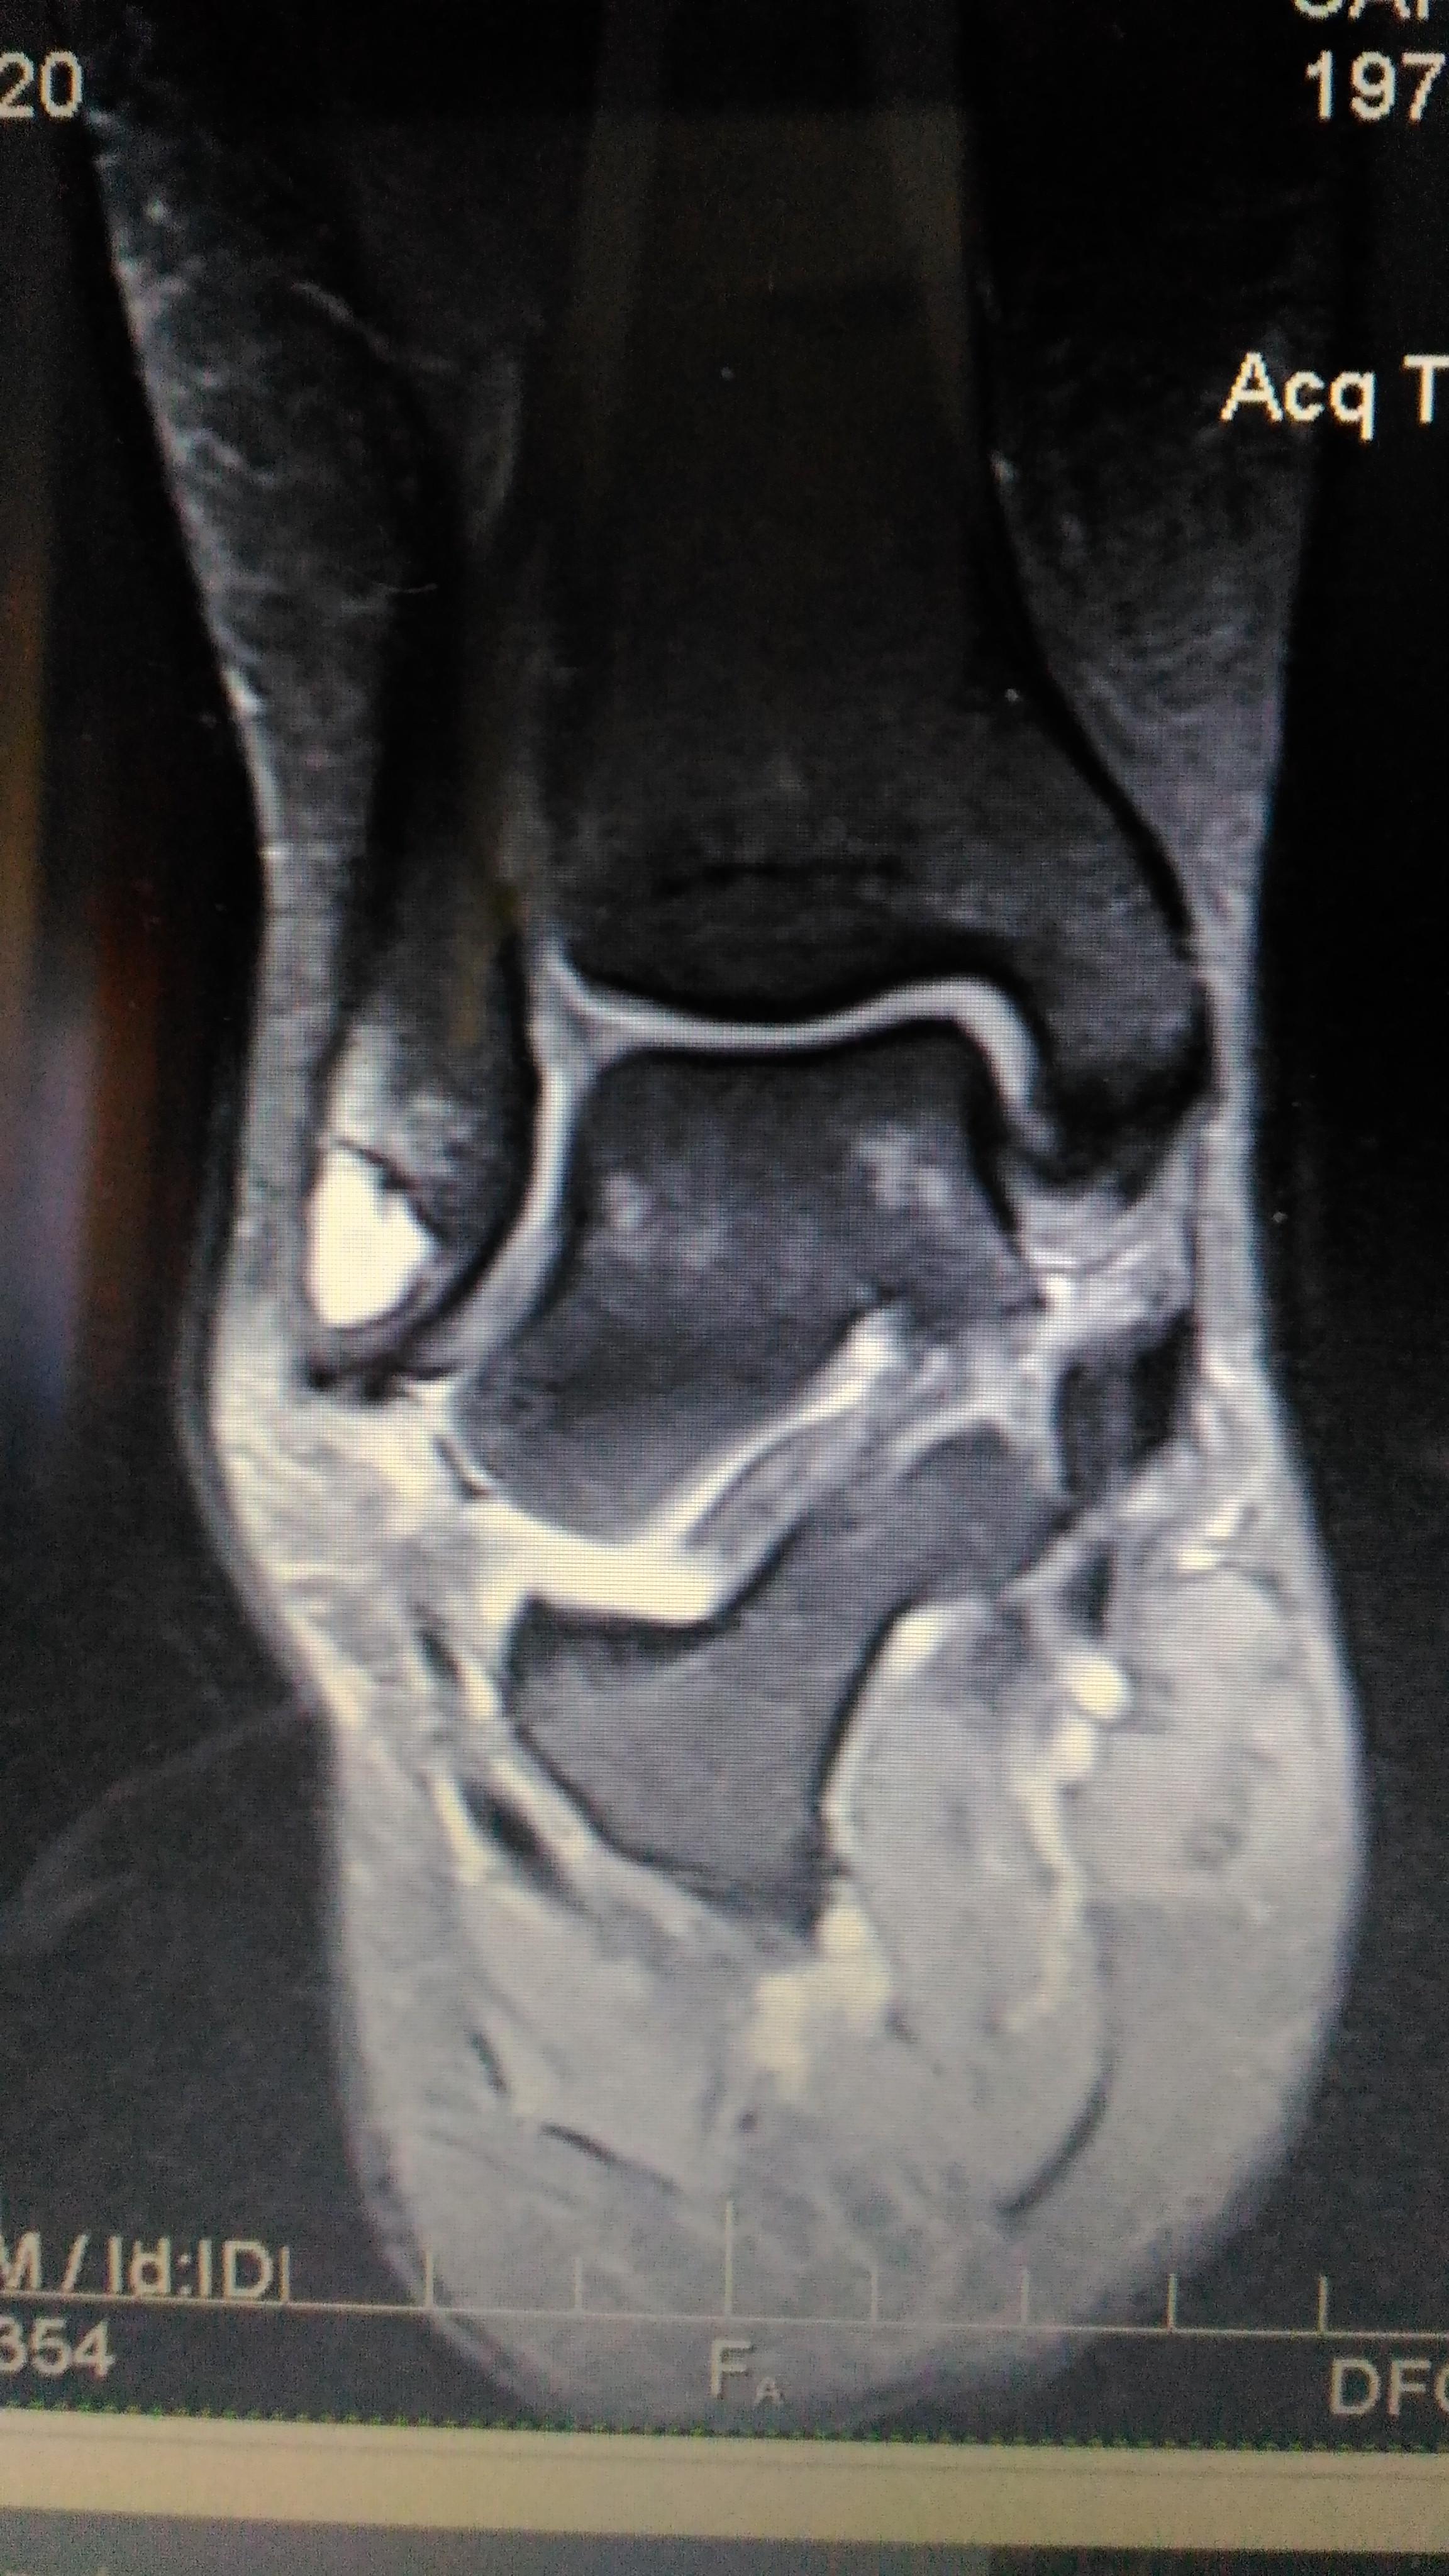

Buongiorno, giocando a pallavolo ho subito una distorsione scendendo da un salto, al momento molto dolore e caviglia gonfia, ma dopo un paio di giorni gonfiore di molto diminuito e nessun ematoma visibile.

Di conseguenza non ho fatto nessun controllo nell'immediato, ma permanenti una certa dolorabilita dopo un mese sono andata dall'ortopedico che trova una caviglia instabile e sospettando qualche lesione richiede una Rmn di cui riporto l'esito per un vostro parere. Preciso che dal trauma alla risonanza sono passati circa 50 gg.

Disomogeneità delle contrapposte superfici articolari della tibio tarsica come per condropatia degenerativa; a tale livello si rileva un diffuso impegno reattivo sinoviale con modica quota fluida che si raccoglie prevalentemente nei recessi laterali e posteriori dell'articolazione.

Alterazioni evolutive condrali di entità significativa si rilevano anche in corrispondenza della astragalo navicolare e della sottoastragalica.

In tale contesto si apprezzano fenomeni di riassorbimento distrofico cistico dell'osso subcondrale a livello dell'apice del malleolo peroneale, verosimile sede di pregressa infrazione sul punto di inserzione del PAP.

In corrispondenza del seno del Tarso si apprezza un alterazione di segnale come per impegno reattivo a carattere infiammatorio con parziale obliterazione del tessuto adiposo tarsale (iniziale involuzione fibrosa).

Disomogeneità del tendine tibiale posteriore specie in prossimità della sua deflessione malleolare come per tendinosi con presenza di fenomeni reattivi lungo il decorso della struttura tendinea.

Lungo il decorso dei tendini peronei si apprezza un impegno flogistico di modesta entità.

Aspetto cicatriziale del PAA, del PC e del deltoideo.

Lieve tendinosi achillea.

Buongiorno Alessia, purtroppo gli esiti della RMN non sono positivi.

In parole povere la RMN ci dice che hai avuto una lesione del Legamento Peroneo Astragalico Anteriore (PAA) del Legamento Peroneo Calcaneare (PC) e del Legamento Deltoideo.

Si sono cicatrizzati, ma verosimilmente sono cicatrizzati lunghi e per cui danno nstabilità della TT.

E' presente inoltre una grave condropatia della cartilagine della caviglia e una pregressa frattura del perone stabilizzata.